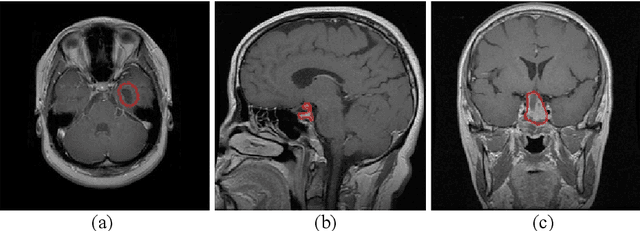

According to the World Health Organization, cancer is the second leading cause of death worldwide, responsible for over 9.5 million deaths in 2018 alone. Brain tumors count for one out of every four cancer deaths. Accurate and timely diagnosis of brain tumors will lead to more effective treatments. To date, several image classification approaches have been proposed to aid diagnosis and treatment. We propose an encoder layer that uses post-max-pooling features for residual learning. Our approach shows promising results by improving the tumor classification accuracy in MR images using a limited medical image dataset. Experimental evaluations of this model on a dataset consisting of 3064 MR images show 95-98% accuracy, which is better than previous studies on this database.